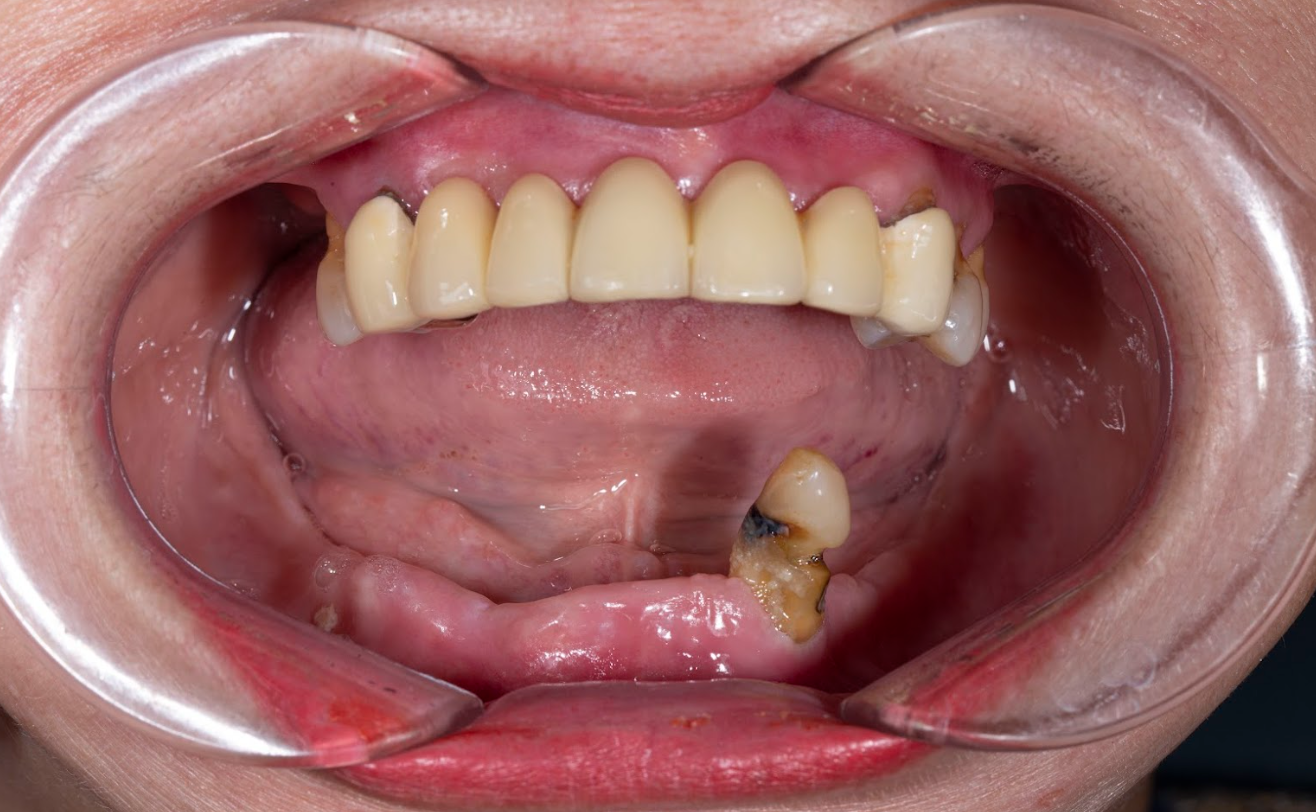

Trường hợp mất răng của cô Nguyễn Kim Hoa (64 tuổi; Hoàn Kiếm- Hà Nội); Trồng Implant toàn hàm dưới

Tình trạng:

01/06/2025: Cô Kim Hoa đến đến phòng khám gặp ThS BS Phạm Hùng Sơn với tình trạng răng:

*Hàm trên

+ Hàm trên tiêu xương nhiều

+ 2 răng số 7 hàm trên đều mất hết (R17, 27)

+ Toàn bộ cụm răng cửa từ răng số 4 bên trái sang bên phải 8 răng đều đã điều trị tủy cắm chốt

+ Răng số 6 hàm trên bên phải (R16) sâu to sát tủy

*Hàm dưới:

+ Hàm dưới tiêu xương nhiều

+ Răng số 5 bên trái (R35) và răng số 4 bên phải (R44) gãy chân

+ Răng số 5,6,7 hàm dưới bên phải (R45,46,47) mất

+ Răng số 6,7 hàm dưới bên trái (R37, 36) mất

Kế hoạch điều trị:

+ Chia thành 2 đợt điều trị cấy toàn hàm dưới trước

+ Trồng răng toàn hàm dưới 6 trụ Neodent của Thụy Sỹ: 22,5 Triệu x 6 = 135 Triệu

+ Làm hàm sứ rời Zirconia 12 răng: 54 Triệu

Tổng chi phí điều trị trồng răng toàn hàm trên: 135 Triệu + 54 triệu = 189 Triệu